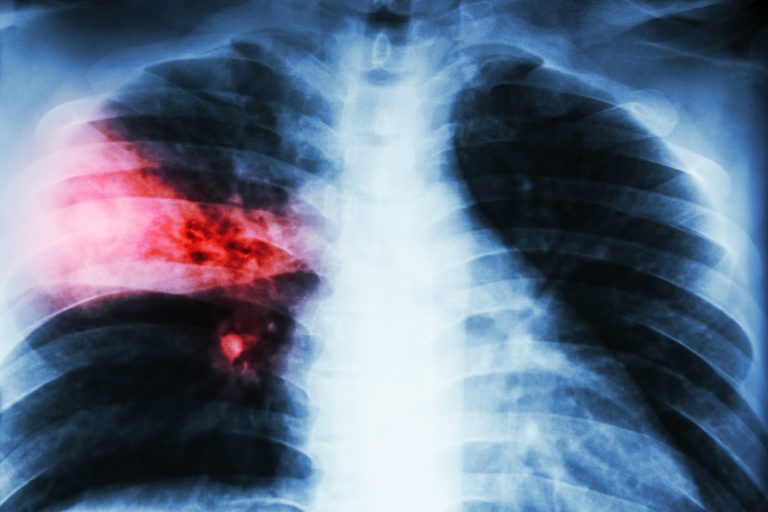

This article was taken from: https://www.theguardian.com/science/2020/jan/09/china-pneumonia-outbreak-may-be-caused-by-sars-type-virus-who By Guardian News World Health Organization says a new coronavirus, the family linked to Sars and Mers, may be behind Wuhan cases A cluster of more than 50 pneumonia cases in the central Chinese city of Wuhan may be due to a newly emerging member of the family of viruses that…

This article was taken from: https://www.dailymail.co.uk/news/article-7676093/amp/Furious-backlash-emerges-Google-secretly-amassed-healthcare-data-millions-people.html By Nicola Davis A&E admissions highest in deprived areas of England as bronchiolitis drives increase Emergency hospital admissions for children with pneumonia have risen by more than 50% in England over the past decade, figures suggest, with admission rates highest in more deprived areas. According to NHS Digital data…